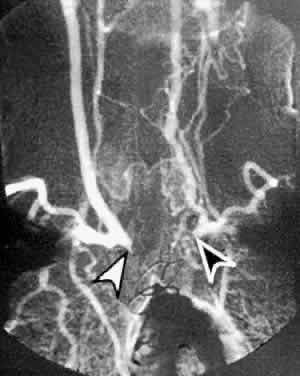

TAKAYASU'S ARTERITIS

Takayasu's arteritis is a rare, chronic inflammatory disease of unknown etiology affecting the large arteries of the body, namely the aortic arch, the descending aorta, the pulmonary artery, and their primary branches. It occurs mainly in young women, and the typical age of onset is 10 to 40 years.55 It appears in all populations, but is more frequently seen in Asians.

The early signs and symptoms of Takayasu's arteritis include fatigue, weight loss, low-grade fever, arthralgias, myalgias, and headaches, and it may be mistaken for juvenile rheumatoid arthritis in a young female patient. The later clinical manifestations of Takayasu's arteritis relate to the anatomic site of vascular obstruction. Decreased blood flow to the brachial arteries results in coldness of the hands, paresthesias, and asymmetric or absent brachial pulses.56 Renovascular hypertension develops in half of patients because of involvement of the renal arteries of the abdominal aorta.57 Occlusion or narrowing of the carotid or vertebral arteries may result in cerebrovascular accident.58

Ophthalmic symptoms, due to ocular hypoperfusion from occlusion of the carotid artery, are seen in 15% of cases.59 These ophthalmic changes may be identical to those of ocular ischemic syndrome caused by carotid atherosclerotic disease (see Figs. 5 and 6).60,61 Arteriography of the aortic arch region, showing smooth-walled areas of stenosis and dilation, is usually necessary to confirm the diagnosis (Fig. 11). Collateral circulation, due to the chronicity of the stenosis, is usually prominent.

Fig. 11. Digital subtraction thoracic angiogram of the aortic arch and its major branches in the same patient with Takayasu's arteritis as shown in Figures 5 and 6. The right common carotid artery shows nearly complete occlusion (white arrowhead). The left common carotid artery shows complete occlusion with extensive collateral flow (black arrowhead). (Courtesy Travis A. Meredith, MD, St. Louis MO)

In cases of rubeosis iridis in which the iridocorneal angle is open, laser photoablative or cryoablative procedures may be considered.9 Takayasu's arteritis in its active stage typically responds well to corticosteroid therapy. In early cases, arterial stenosis may actually reverse and ischemic symptoms improve; however, after fibrous tissue has formed or thrombosis has already occurred, steroids may no longer help. Angioplasty or bypass grafts may be considered in late cases in which irreversible artery stenosis has occurred and significant ischemic symptoms persist.